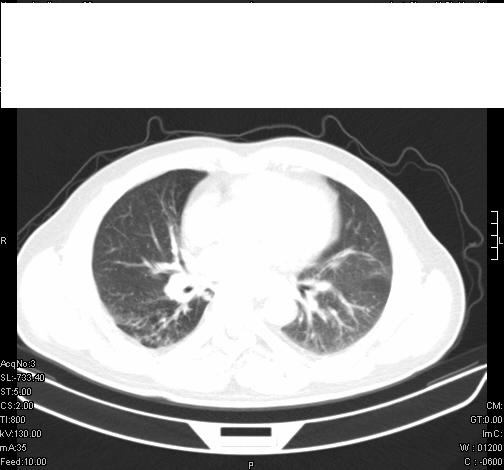

标题: CT6685:右肺阻塞性炎症,增强CT。 [打印本页]

标题: CT6685:右肺阻塞性炎症,增强CT。

前几天,发了患者的平扫片,患者抗炎一周后增强扫描。右中叶病灶吸收明显,但下叶病灶未见明显吸收。右肺门可见结节影,看来凶多吉少

病灶在下叶,散发,抗炎治疗有效,考虑炎症,楼主说的肺门结节看的不明显

右肺下叶散在的斑片状致密影,下叶支气管变窄。考虑:右肺慢性炎症。

第18幅,好像不能简单用炎症解释,前几天我发平扫时,90%人支持肺癌,现在好像大家更倾向于炎症了,我觉得还是不能排除肺癌。